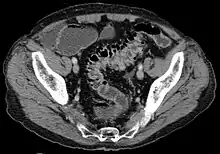

CT scan showing extensive diverticulosis of the sigmoid colon

Diverticular disease

• Contrast CT is the investigation of choice in acute episodes of diverticulitis and where complications exist.